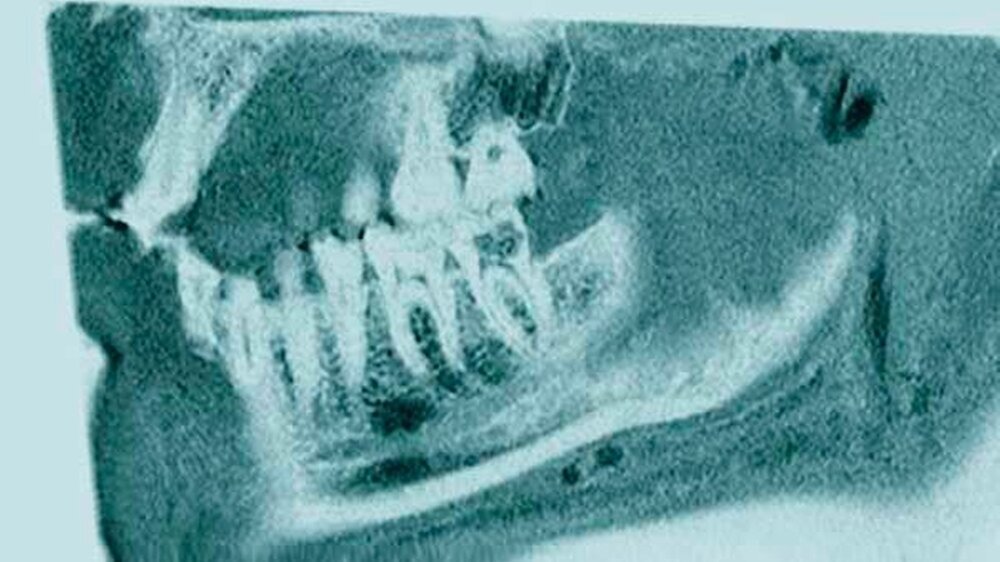

Die Auswertung des Knochenverlusts ergab einen Unterschied zwischen den Werten, die in der OPT gemessen wurden, und denen aus den MRT-Aufnahmen von circa vier Prozent. Es besteht jedoch nur eine begrenzte Vergleichbarkeit der beiden Bildgebungsmodalitäten, da es sich beim Verfahren der OPT-Bildgebung um ein zweidimensionales Verfahren mit zusätzlichem Verzerrungsfaktor und bei der MRT um ein dreidimensionales Schnittbildverfahren handelt. Besser wäre der Vergleich MRT zu DVT gewesen, der uns leider nur sehr vereinzelt vorlag (Abbildungen 2 und 3).

Definiert wurde eine generalisierte Parodontitis, wenn ein Attachmentverlust an zwei oder mehr als zwei interdentalen Stellen nicht benachbarter Zähne festzustellen war und/oder eine Taschensondierungstiefe (TST) von > 3 mm an der oralen oder an der lingualen Position auftrat. Aktuelle OPT-Aufnahmen wurden in die Auswertungen einbezogen (sofern verfügbar) und durch die Patienten zur weiteren Evaluation zur Verfügung gestellt. Die MRT-Untersuchungen wurden am Klinikum rechts der Isar in der Abteilung für Diagnostische und Interventionelle Neuroradiologie an einem 3T-MRT-Scanner (Elition, Philips Healthcare, Best, Niederlande) durchgeführt, wobei eine 16-Kanal-Kopf-Hals-Spule verwendet wurde. Es wurden je zwei Sequenzen aufgenommen, wobei die eine der Darstellung von Knochen dediziert ist (T1 FFE Black bone, 3D isotrope Sequenz mit 0,43 x 0,43 x 0,43 mm Voxelgröße) und die andere sehr sensitiv intraossäre Ödeme detektieren kann (T2 STIR, 3D isotrope Sequenz mit 0,65 x 0,65 x 0,65 mm Voxelgröße). Die Aufnahmezeit betrug circa fünf bis sechs Minuten pro Sequenz, so dass der Patient insgesamt circa zwölf Minuten im Scanner verbrachte. Die Applikation von Kontrastmittel war nicht notwendig.